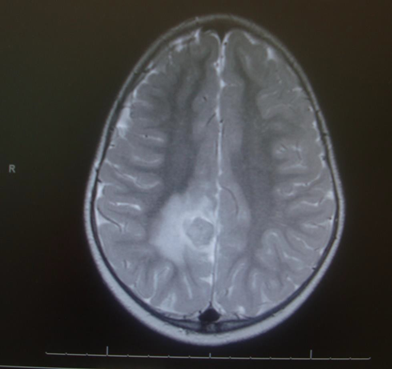

On cranial CT, PML lesions may appear as hypodense patchy or confluent white matter regions. Typical MRI features include single or multiple non-enhancing, non-space-occupying, predominantly white matter lesions commonly involving the frontal and parieto-occipital subcortical white matter.